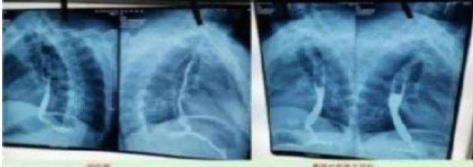

这是治疗前:病变长约 7 ㎝。从吃饭困难到滴水不 进。

2023 年 10 月 9 日在山西肿瘤检查:病变长度 7 ㎝。从 2023 年 10 月 28 月开始服用中药;2024 年 3 月 24 日拿中药:2024 年 8 月 29 日山西肿瘤医院 复查(病变 7cm 癌变消失)。 目前:吃饭一大碗,一切很好,参加农业劳动。这是一 位贫困山村的农妇。

食道癌患者从吃饭困难到滴水不进。经两次治 疗:7 公分的食道癌经省肿瘤医院 CT 检查:病灶消 失。至今每顿一大碗,馍头,面条。米饭都能,并时 常参加农业劳动!两个月临床治愈! 患者送上锦旗以表对陈海林医生的感谢 案例 3.、近日,陈海林教授中医治疗成功挽救重症患者的消 息引起了广泛关注。据悉,该患者陈香花在经历了西 医的多次手术、化疗和放疗之后,身体状况急剧恶化, 最终被多家医院拒之门外。在生命即将走到尽头的时 候,被好心人送到陈海林中医诊所。更严重的是该患 者有多种严重疾病缠身,包括失去右肺、左肺功能仅 剩三分之二,并伴有心脏病、贫血、高血压等十多种 基础疾病,生命垂危。面对这样一位多种病且复杂的 危重患者,陈海林教授秉承救命优先的原则接诊了这 位患者,经过仔细的辨证施治,陈教授为患者制定了一 套个性化的中医治疗方案,在经过长达七个月的纯中 医治疗后,患者竟奇迹般地恢复了健康,重新获得了新 生,也创造了中医药治疗重症肺癌的奇迹。

上图是服用两个月中药的前后对比图